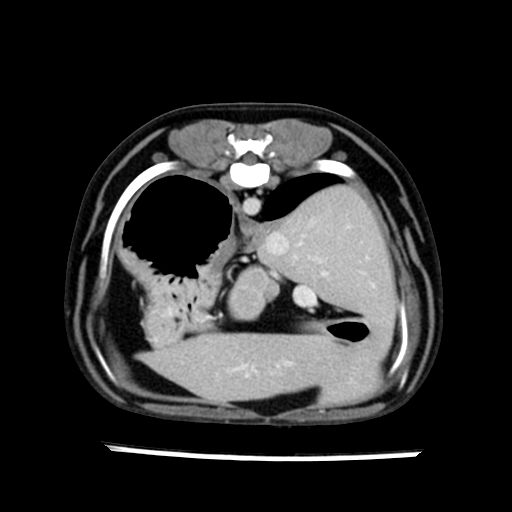

prescritto esame TAC

sequenza immagini limitata al fegato reni e surreni

le immagini ecografiche rispetto alla tac datano circa 7 mesi prima ,le surrenali sono normali nonostante il test acth sia risultato positivo .all’esame TAC dopo diversi mesi risultano aumentate armonicamente nel volume e si individua un forte sospetto di adenoma ipofisario .

sospetto adenoma ipofisario vs. meno probabilmente meningioma della base; intertiziopatia polmonare; lesione espansiva epatica, verosimilmente del lobo laterale sinistro, di sospetta natura neoplastica; lesioni spleniche di natura da definire; iperplasia/ipertrofia delle ghiandole surrenali, bilateralmente; vertebra di transizione del rachide toracico; tenosinovite cronica del muscolo bicipite brachiale di destra.